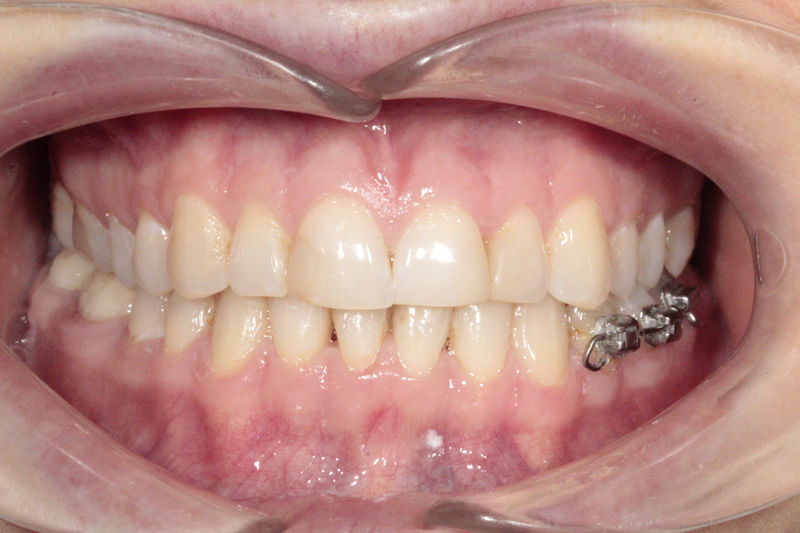

Implantes, ortodoncia y coronas.